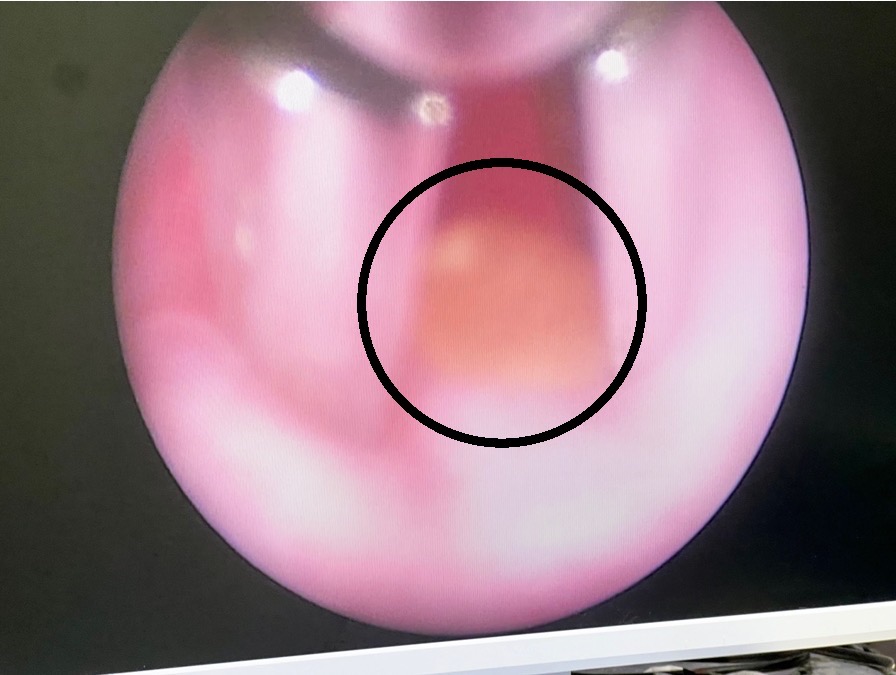

藉由內視鏡的鏡頭,可清晰的看見結石並以夾取鉗取出(圖四),相較於傳統手術需透過觸摸來探查結石,微創手術大幅縮短了麻醉及術後恢復的時間。

圖四、內視鏡下可清楚的看見結石,並使用夾取鉗取出結石。